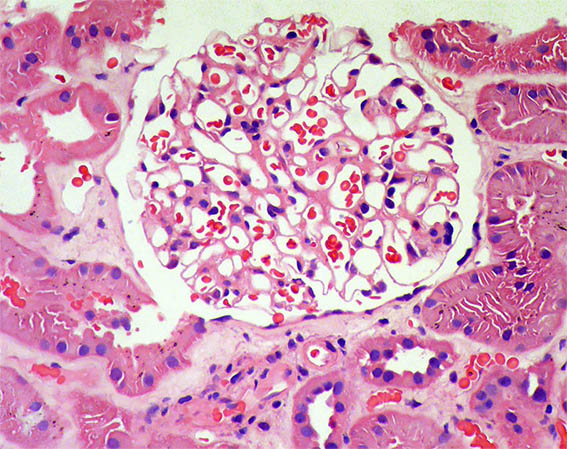

Figure 1. H&E, X100.